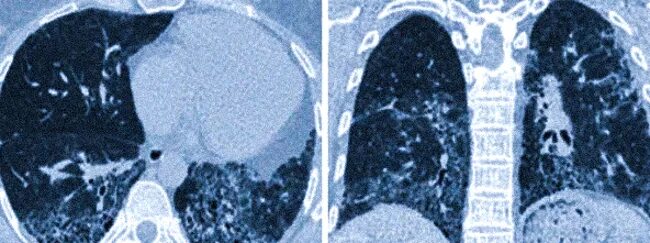

Гипостатические изменения кт